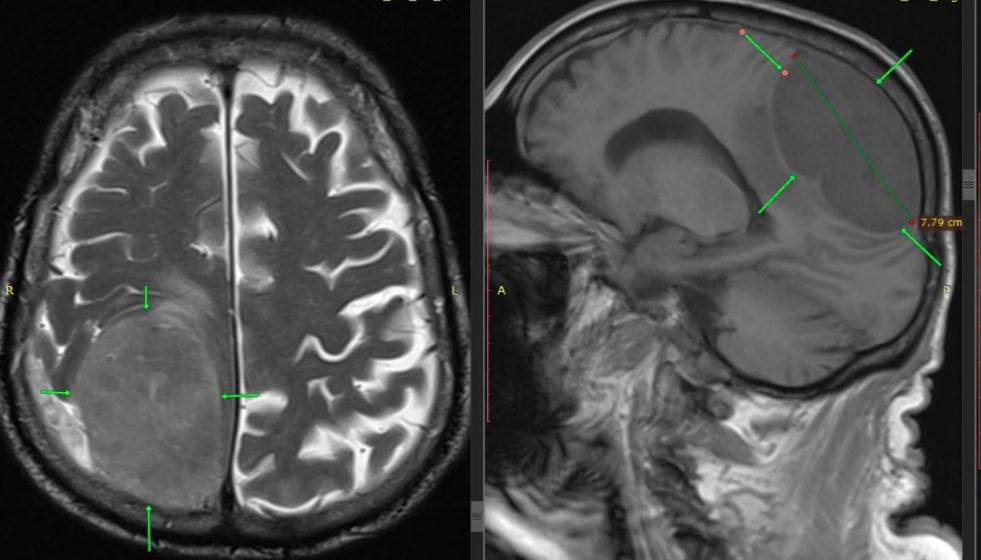

85-летний мужчина поступил в больницу, когда у него уже отказала левая нога и левая половина тела. В первые минуты было подозрение на инсульт, но экстренное обследование показало гигантское новообразование (87см) в правой теменно-затылочной области мозга, отвечающей за движение левой половины тела.

Нейрохирурги выполнили костно-пластическую трепанацию черепа и полностью удалили опухоль.